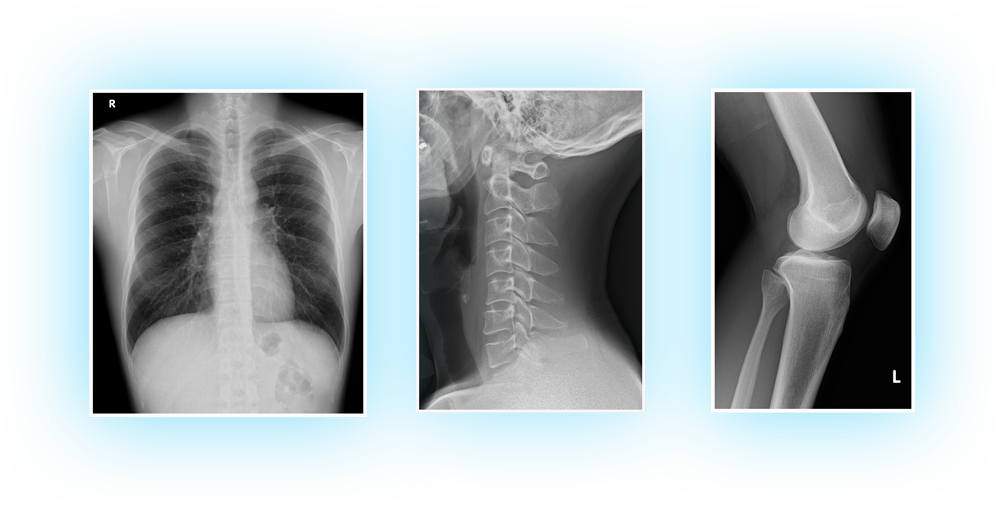

一般撮影

「より少ないエックス線の量で、より高画質に」

胸部や腹部、全身の骨などの撮影を行っています。

健康診断などで胸部の撮影をされた経験は皆さんあると思いますが、撮影する部位は頭から足先まで全身が対象です。

撮影機器の新規導入により、以前よりも少ないX線量で、より高画質な画像が撮影可能となりました。

- 胸部や腹部、骨などの単純エックス線撮影を行う装置です。

- FPD(フラットパネルディテクター)を用いた撮影システムを導入しており、従来よりも高画質でより少ない被ばく線量で撮影することができます。

- 単純撮影室は6部屋あり、患者様の待ち時間短縮に努めています。